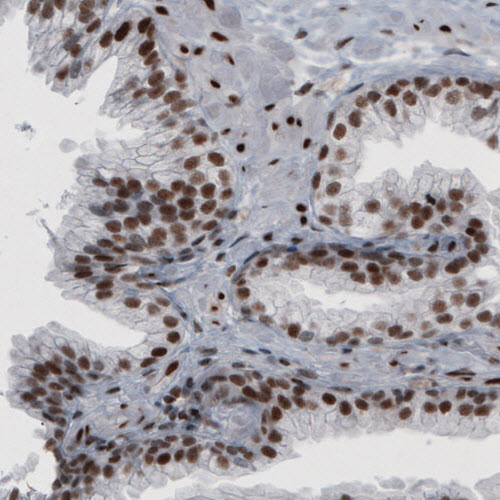

Immunohistochemical staining of human fallopian tube shows strong nuclear immunoreactivity in glandular and connective tissue cells.